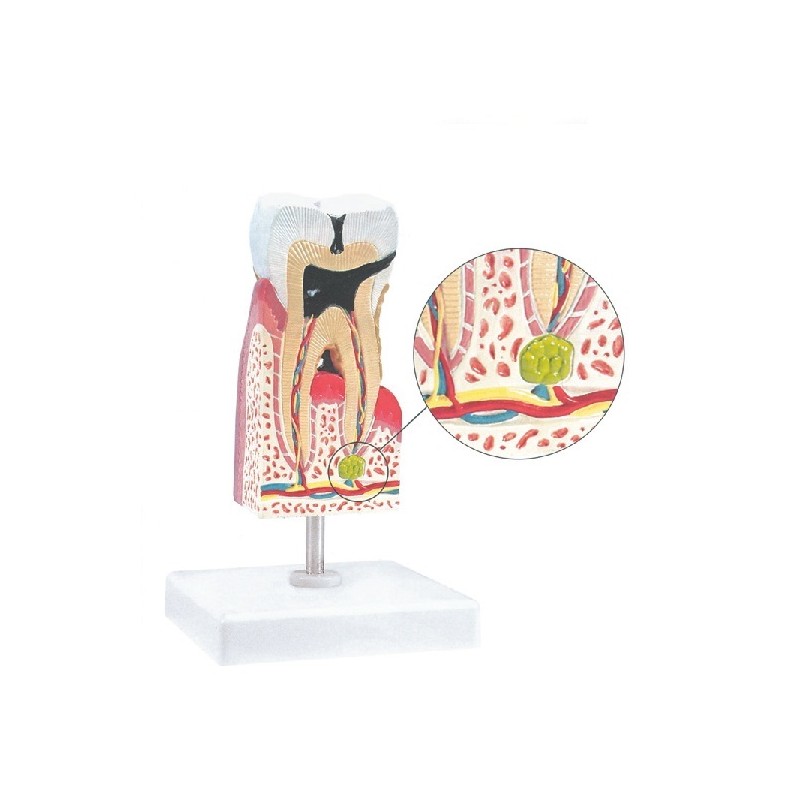

GIMA MODELLINO ANATOMICO MOLARE INFERIORE CON CARIE

56,89 € +IVAQuesto modello a 1 pezzo è approssimativamente 10x della grandezza naturale e mostra le patologie più importanti dei denti, comprese le carie dentali, pulpite, gengivite e parodontite periapicale.